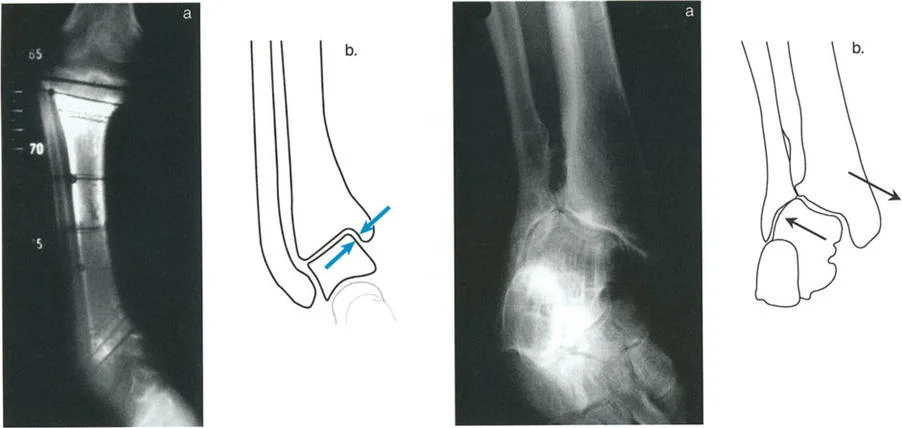

* الأشعة السينية الجانبية والامامية الخلفية للكاحل: تُظهر هذه الصور تفاصيل مفصل الكاحل نفسه، بما في ذلك زاوية القصبة الأمامية البعيدة (ADTA) وزاوية القصبة الوحشية البعيدة (LDTA)، وهي زوايا حاسمة لتحديد التشوه في المستويين الأمامي والسهمي.

أنواع جراحات قطع العظم فوق الكاحل (Supramalleolar Osteotomy)

جراحة قطع العظم فوق الكاحل (SMO) هي الإجراء الأكثر شيوعًا لتصحيح تشوهات قصبة الساق البعيدة. تتضمن هذه الجراحة قطعًا دقيقًا في عظم الساق (القصبة) فوق مفصل الكاحل مباشرة، ثم إعادة محاذاة العظم وتثبيته في الوضع الصحيح. هناك عدة أنواع من هذه الجراحة: